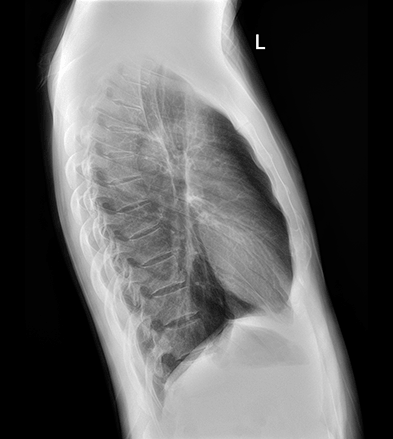

平板探测器

超大尺寸

超范围

超高像素

高清点片